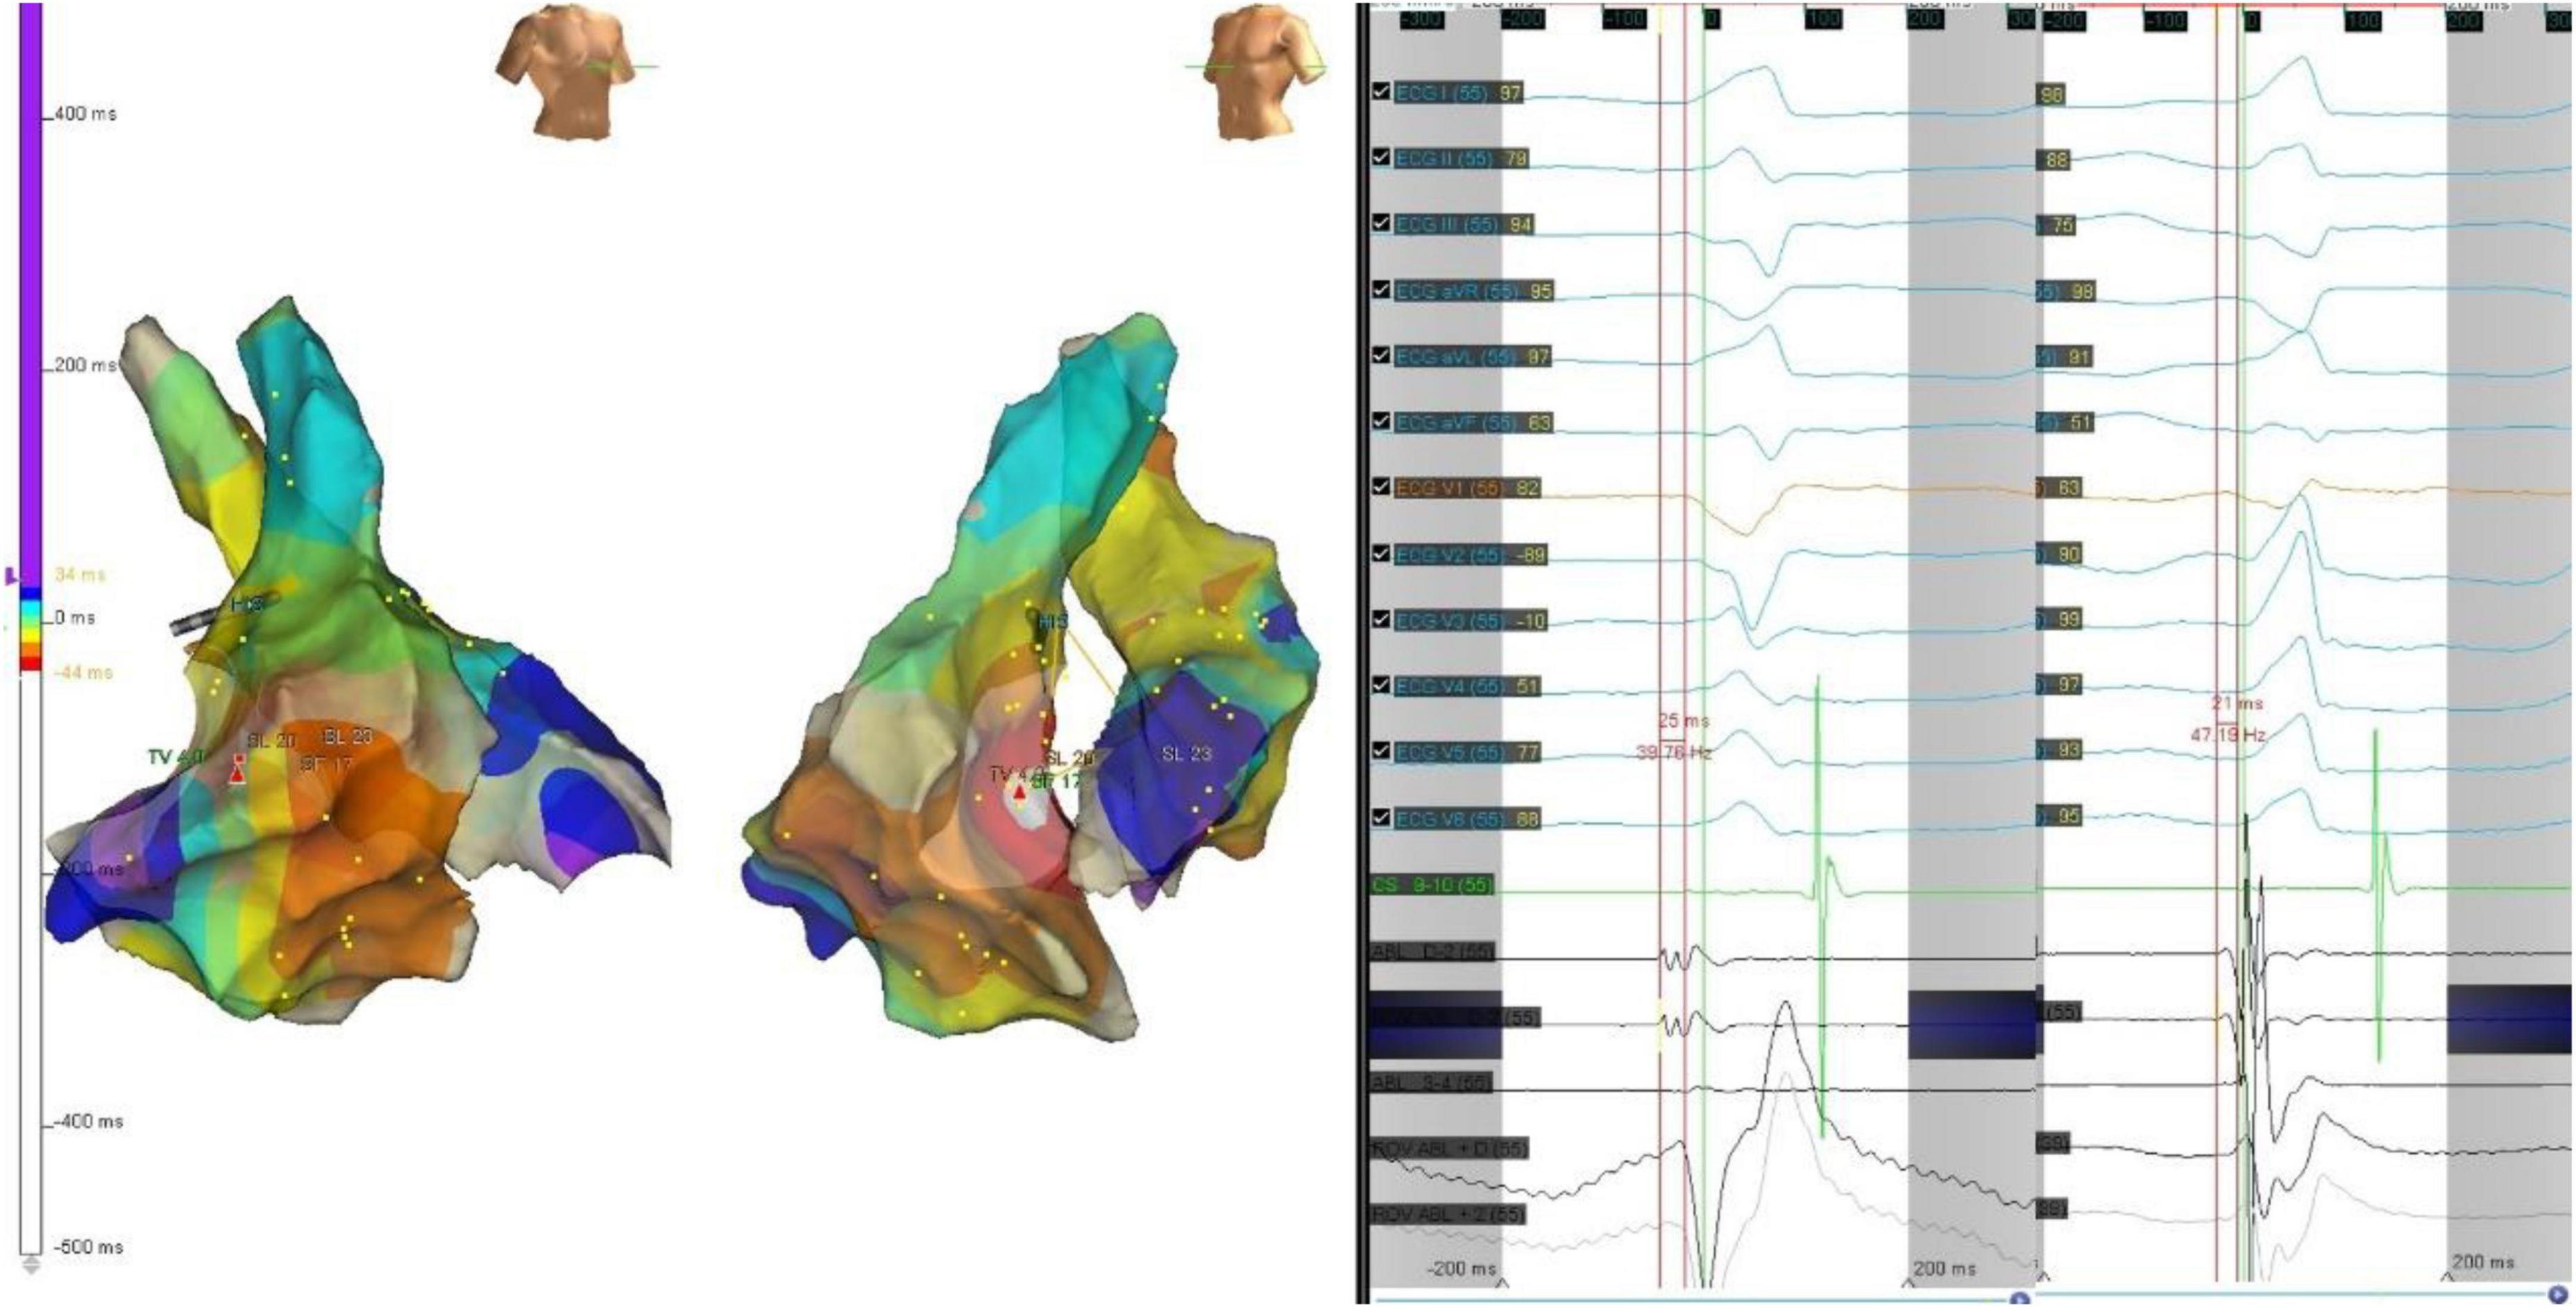

Figure 5. The precordial R wave transition occurred at V3 in ECG (left) before first ablation. Electroanatomic mapping in the right ventricle and the left ventricle, the earliest activation site was located at right basal septum with a preceding time compared with the onset of the QRS wave of 25 ms. After initial ablation failed, the precordial R wave transition occurred at V2 in ECG (right). Remapping at the bilateral side of the basal septum was performed. The earliest activation site was located at left basal septum with a preceding time compared with the onset of the QRS wave of 21 ms. The PVC was successfully eliminated by ablation of both sides of basal septum.